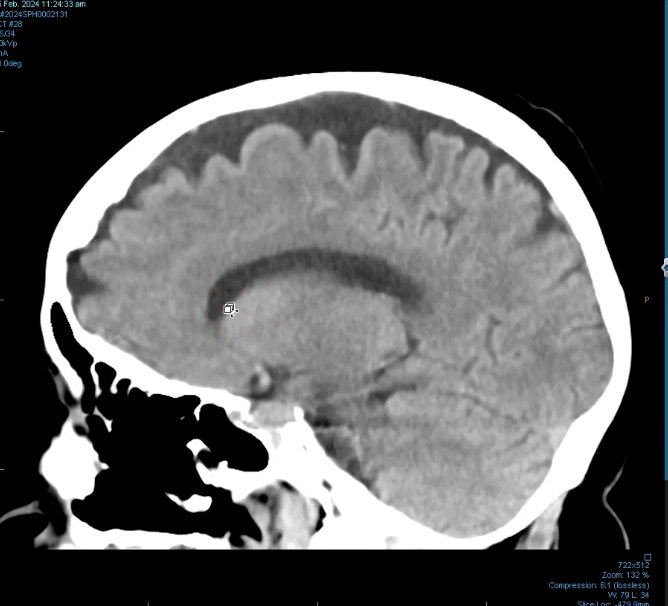

New cards

<p></p>

superior saggital sinus- part of venous system of brain trains blood from lateral aspect of anterior cerebral hemispheres to confluence of sinus.